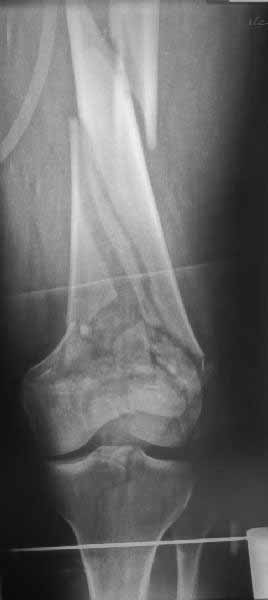

И не обратите, коллега, пока не сделаете четкие анфасные снимки (лучше с дистракцией) где будет четко визуализироваться малоберцовая кость. Думается, что и КТ здесь будет уместно, дабы не пропустить возможное флексионное повреждение (перелом Hoffa).

>Сразу не обратил ваше внимание именно на это, что сломаны оба мыщелка, и больший является именно медиальным мыщелком

А теперь по поводу лечения перелома. Среди всех чрез/меж-мыщелковых переломов в 38% сопровождются переломом в корональной плоскости, т.е перелом Hoffa. Nork et al, J Orthop Trauma, 87:564, 2005.

У больных как в этом случае, с вовлечением двух мыщелков правильно, что сделали вытяжение до операции. Здесь имеется флексионный компонент на другой стороне, и я бы рекомендовал операцию делать из двух доступов. Сперва фиксировать медиальную колонну custom made пластиной, обычно 1/3 тубулярной пластиной в 4.5 мм, потому что пока производители опаздывают с медиальной пластиной.